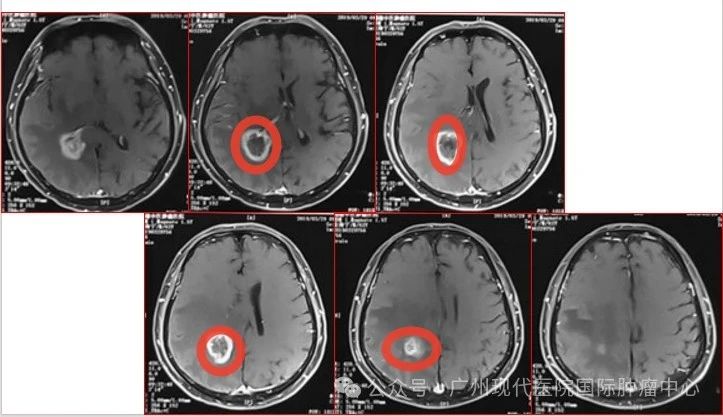

2015-11,头颅MR检查提示颅内转移

2018-11,颅内肿瘤进展,无法接受后续治疗

2019-3,接受脑瘤粒子植入术

2019-7,颅内肿瘤基本消失,正常生活至今

2019年7月,颅内肿瘤已基本消失